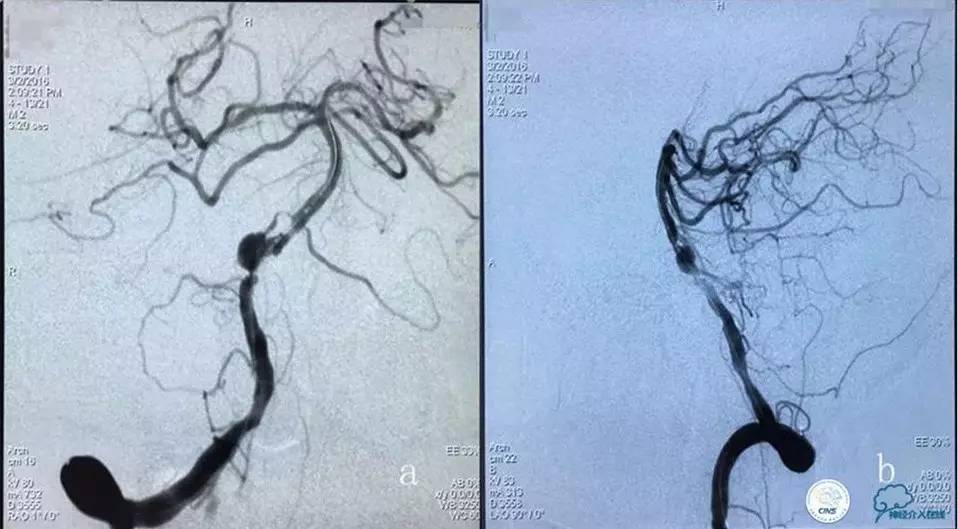

入院后造影检查:

右侧颈内动脉正侧位造影显示:右侧颈内动脉C1段狭窄并溃疡斑块形成,狭窄率约95%,狭窄长度约36mm。

左侧颈内动脉三维旋转后选取工作位角度造影:左侧大脑中动脉分叉部宽颈动脉瘤,大小约8.13mm×7.45mm,瘤颈5.35mm,且上有籽瘤。

血管内治疗策略:右侧颈内动脉开口狭窄处行球囊扩张支架成形术;左侧大脑中动脉分叉部动脉瘤行LVIS JR支架辅助弹簧圈栓塞动脉瘤。

支架成形术后造影示:支架完全覆盖狭窄段及溃疡斑块,与血管壁贴合良好,残余狭窄率约10%,前向血流较前改善(TICI分级3级)。